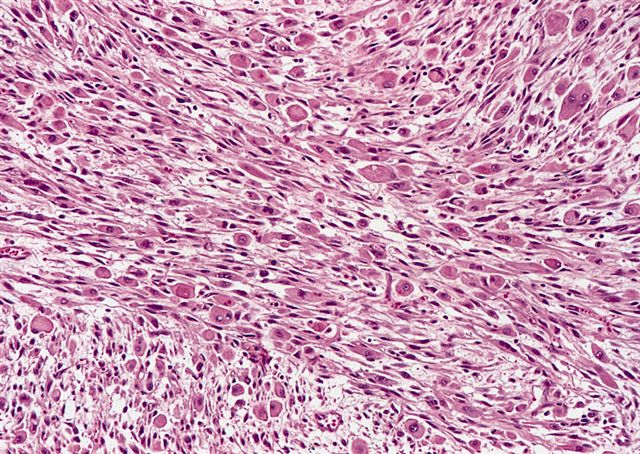

Microscopic (histologic) description

- High grade dedifferentiated liposarcoma

- Well differentiated and dedifferentiated components are often both present and can have abrupt or gradual transitions

- Dedifferentiated component is a cellular and typically a nonlipogenic sarcoma with significant pleomorphism

- Although some propose a mitotic rate of > 5 mitoses/10 high power fields, this is not uniformly adopted (Am J Surg Pathol 2023;47:649)

- Often resembles malignant fibrous histiocytoma (MFH), now referred to as undifferentiated pleomorphic sarcoma (UPS), with short fascicles of pleomorphic spindle cells associated with mixed inflammatory infiltrate

- Can show a peculiar whirling pattern reminiscent of meningothelial structures (Histopathology 1998;33:414, Am J Surg Pathol 1998;22:945)

Microscopic (histologic) images

Contributed by Michael R. Clay, M.D. and AFIP

Board review style question #1

A 10 cm retroperitoneal mass was surgically resected with the histologic appearance shown in the image above. Which one of the following ancillary tests would best help support the diagnostic impression?

Board review style answer #1

D. FISH positive for MDM2 gene amplification. The microscopic image demonstrates a proliferation of variably sized adipocytes admixed with scattered enlarged, hyperchromatic tumor cells that abruptly transitions to a cellular, spindle cell component with significant pleomorphism. These are the key histologic features of dedifferentiated liposarcoma. Detection of MDM2 amplification by FISH is a useful ancillary tool to confirm the diagnosis of both well differentiated and dedifferentiated liposarcoma. It is important to recognize, however, that MDM2 gene amplification is not entirely specific for well differentiated and dedifferentiated liposarcoma as it can also be found in other tumors, including intimal sarcoma, parosteal osteosarcoma, low grade central osteosarcoma, malignant peripheral nerve sheath tumor, endometrial stromal sarcoma and sclerosing rhabdomyosarcoma.